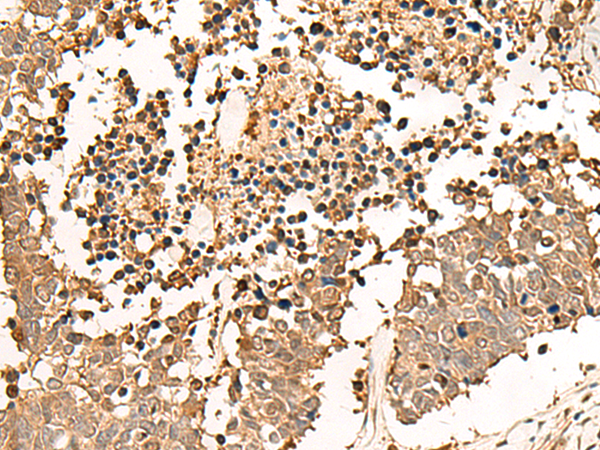

IHC positive control:

Human esophagus cancer and Human lung cancer